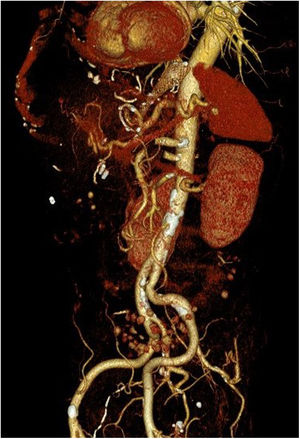

Sin embargo, a las 24 h reingresa por hematemesis con angio-TC normal (fig. 1), realizándose endoscopia que controla la hemorragia mediante clips sin visualizar adecuadamente la endoprótesis. Mediante nueva endoscopia a las 8h, se retira esta y se verifica la hemostasia, aparentemente adecuada. Cinco días después presenta nueva hemorragia con inestabilización, no consiguiéndose control endoscópico, por lo que se decide intervención quirúrgica urgente vía abierta con sospecha de fístula aortoesofágica. La revisión de la angio-TC, previa a la retirada de la endoprótesis, apoya el diagnóstico al objetivar la proximidad de la porción proximal de la misma con la aorta, tal y como se muestra en la reconstrucción 3D (fig. 2). Durante la cirugía, se confirma la fístula, que se repara con sutura aórtica directa. Para su visualización, es preciso deshacer la anastomosis esófago-yeyunal, realizándose esofagectomía, esofagostomía cervical y yeyunostomía de alimentación.